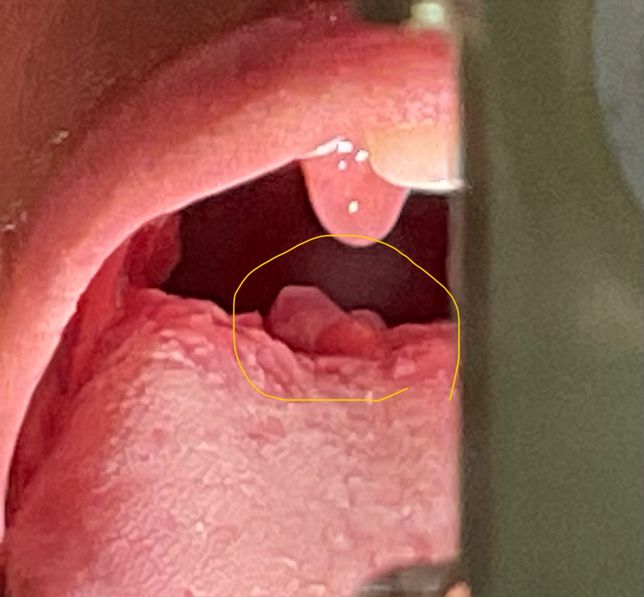

- 약 복용약·영양제Q. 편도염걸렸는데 설편도염은 언제 회복 될까요?편도염이 있다가 이비인후과 가서 약먹고 있다가 몸살이랑 오한증상으로 내과가서 새로처방 받은 약을 먹고 있는데 설편도염도 음식을 삼킬려면 힘든데 언제쯤 괜찮을 까요? 설편도염이 가운데 중앙에 생겼는데 약으로 괜찮아 질까요?(약은 펠프스정, 아모크라정375밀리그램, 소담캡슐 200mg,프리비투스현탁액8ml 총 5일치 약)